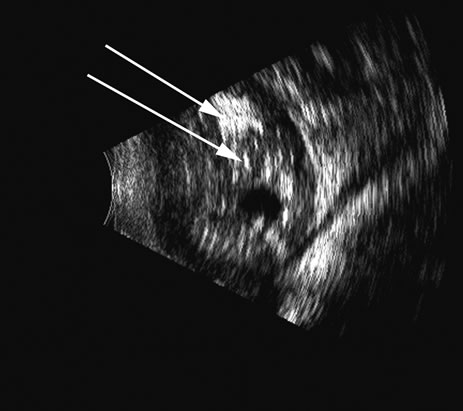

There are several tumors that invade the vitreous or the vitreous space. In children, retinoblastoma can seed the vitreous; in adults, reticulum cell sarcoma can cause vitreous clouding but is nondiscernible from other forms of debris. A very high percentage of retinoblastomas contain calcium, which is very reflective (Fig. 20). Malignant melanoma, hemangioma, metastatic carcinoma, and subretinal hemorrhage can all present with elevated convex lesions that protrude or extend into the vitreous space and are the four most commonly seen posterior segment tumors. Anteriorly, medulloepithelioma (diktyoma) and melanocytoma or ciliary body cysts can also protrude into the vitreous. The differentiation of these tumors has been well described with conventional combined B- and A-scan ultrasound techniques2 and standardized A-scan echography,28 as well as more modern spectral analysis techniques. These all provide excellent means of differentiating solid from cystic lesions, but differentiation between diktyoma (medulloepithelioma), melanocytoma, and melanoma is not possible with A-scan or B-scan.

Fig. 20. An eye filled with a retinoblastoma, which has considerable calcium deposits that produce a very reflective, high-amplitude echogenic structure (arrows).